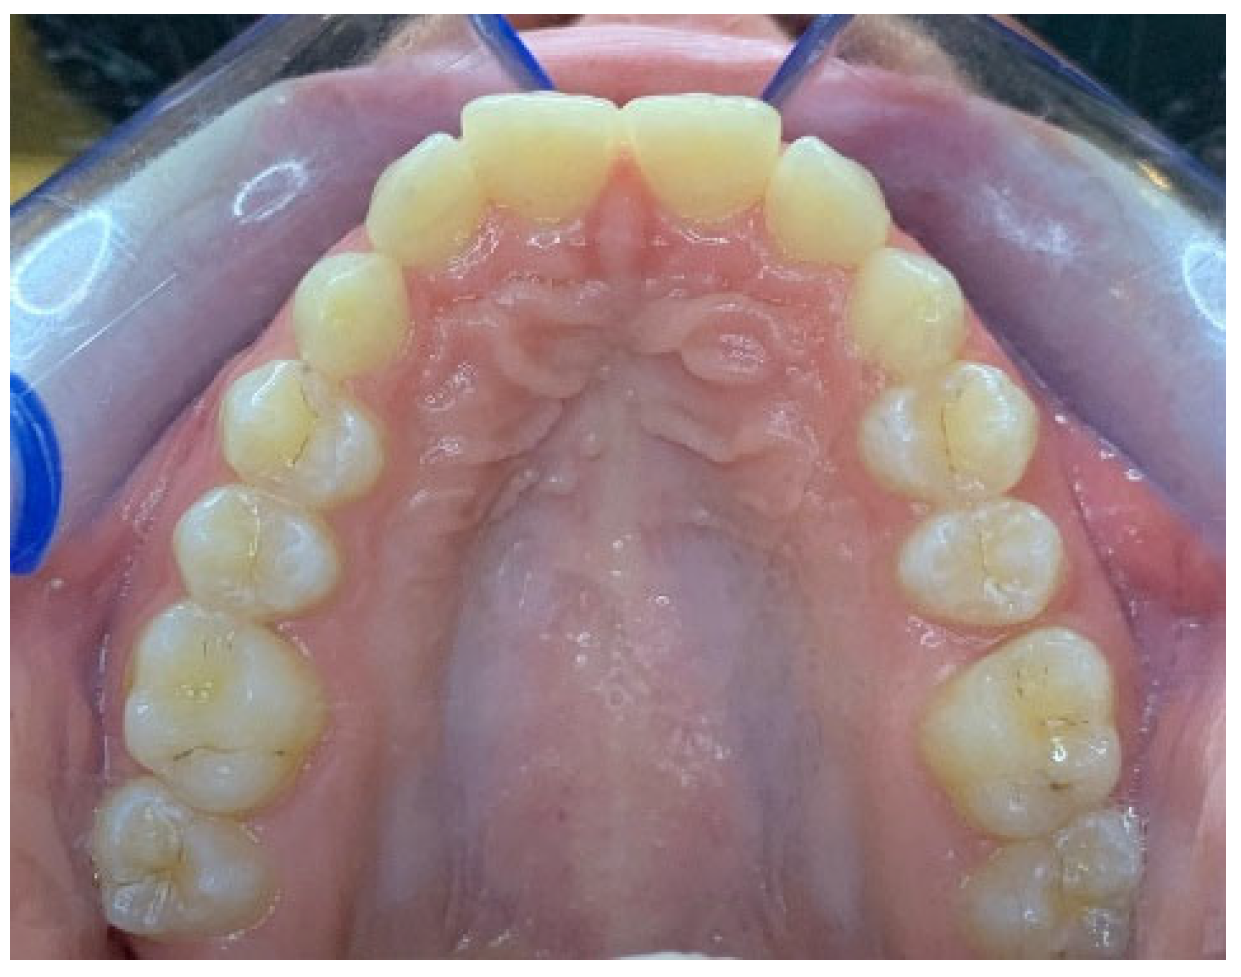

Three-dimensional digital impressions were performed with the intraoral scanner Medit i700 (Medit Corp., Seoul, Republic of Korea) and the initial photos were taken (Figure 3). The patient was informed through surgical consent about the risks and benefits of the operation.

Figure 3. Intraoral occlusal photo of the patient before surgery.